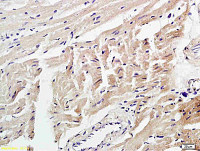

IHC-P analysis of human tonsil tissue section using GTX02727 Topoisomerase II alpha antibody [TOP2A/4397R].

IHC-P analysis of human lymph node tissue section using GTX02727 Topoisomerase II alpha antibody [TOP2A/4397R].